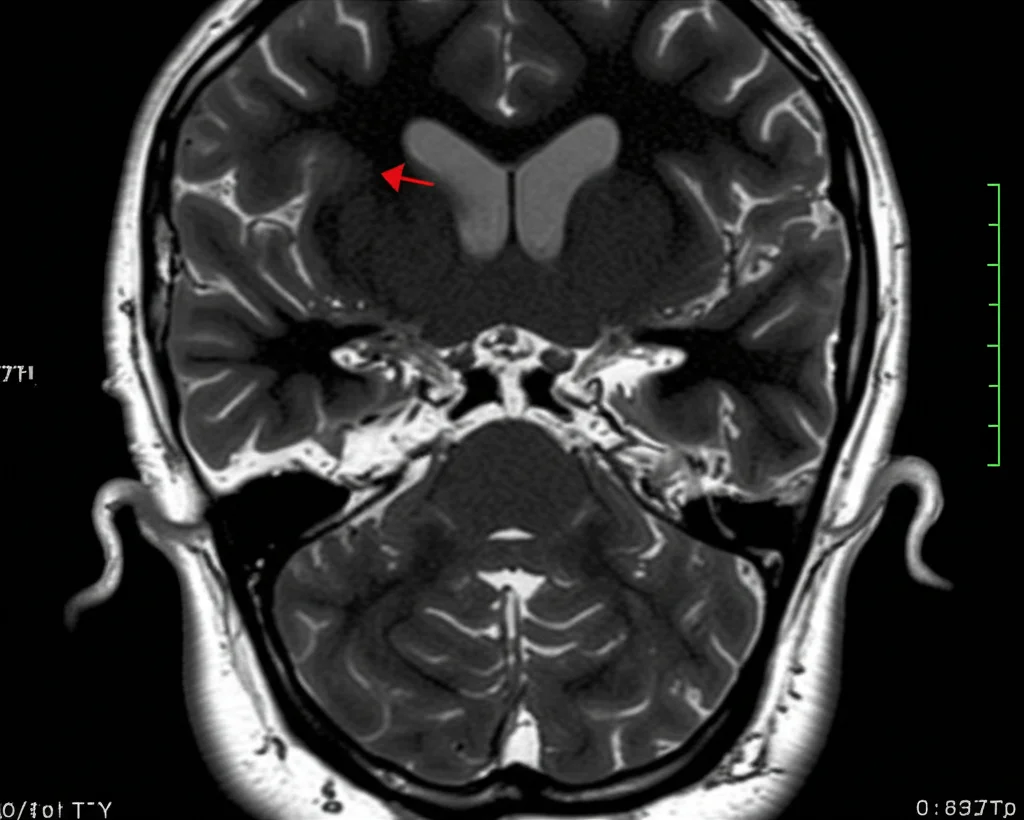

Ciao a tutti! Oggi voglio parlarvi di un argomento affascinante e un po’ di nicchia nel campo della neurochirurgia: le fistole arteriovenose durali intracraniche, o più semplicemente DAVF. Sembra un nome complicato, vero? In pratica, si tratta di connessioni anomale tra arterie e vene nella dura madre, la membrana più esterna che riveste il nostro cervello. Pensate a un groviglio di tubi dove il sangue non scorre come dovrebbe.

Queste DAVF rappresentano circa il 15% di tutte le malformazioni vascolari cerebrali e possono causare un bel po’ di problemi. Il flusso sanguigno anomalo può portare a ipertensione venosa, ovvero un aumento della pressione nelle vene, che a sua volta può dilatare i capillari a monte. Le cause? Non sono chiarissime, ma si pensa possano essere legate a infiammazioni, trombosi (coaguli di sangue) o traumi dei seni durali (i grandi canali venosi del cervello). Un’altra teoria suggerisce che una ridotta perfusione di sangue (ipoperfusione) possa stimolare la creazione di nuovi vasi sanguigni (angiogenesi).

Il rischio principale associato alle DAVF, soprattutto a quelle definite “ad alto grado”, è l’emorragia intracranica. Il tipo di drenaggio venoso è cruciale per determinare il rischio. Usiamo la classificazione di Borden per capire quanto sia “pericolosa” una fistola:

Spesso si usano queste tecniche in combinazione. La SRS, in particolare la Gamma Knife Radiosurgery (GKRS), si è dimostrata efficace, specialmente per le DAVF a basso rischio, con tassi di obliterazione completa (cioè chiusura totale della fistola) che vanno dal 50 all’80% in pazienti selezionati. È fantastico, vero? Un raggio di luce (beh, radiazioni!) che risolve il problema senza bisturi.

Ecco il punto cruciale. A volte, nonostante la SRS, la fistola non si chiude completamente. Rimane un “residuo”. Che fare allora? Si può tentare con l’embolizzazione o la chirurgia, ma c’è un’altra opzione intrigante: ripetere la radiochirurgia stereotassica. Fino a poco tempo fa, non c’erano molti dati sugli esiti di un secondo trattamento SRS per le DAVF residue.